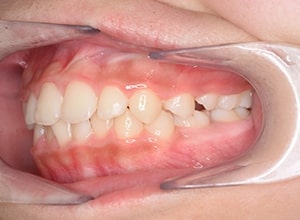

| 口腔内所見 | over jet 3.5mm,over bite4.0mm、下顎正中右側偏位2.0mm、大臼歯関係は左側Ⅰ級であったが、右下6は右下E早期喪失のため近心傾斜しておりⅢ級の臼歯関係となっていた。また上下顎前歯は軽度の叢生を呈していた。 |

| パノラマ所見 | 右下5は右下6近心傾斜により萌出部位不足が認められた。上下顎8歯胚が確認できた。 |

| 批評・予后 | 右下5及び7の萌出前に右下6を整直させることによって、右下5の自然萌出が可能となり正常咬合への咬合誘導が行えたと思う。 |